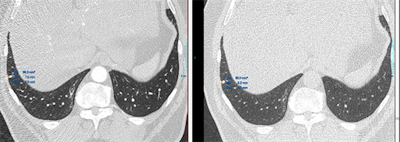

Top images: The semiautomatic lung nodule volumetry tools provides different volume and 2D measurements in different cardiac phases. In the first image, the volume measured is of 89.3 mm3 and in the second, is of 63.3 mm3. All images courtesy of Dr. Diana Penha. Bottom images: The semiautomatic lung nodule volumetry tools provides different volume segmentation that is aberrant in the first image. Due to this aberrant segmentation, the software provided different volumes and 2D measurements."Nowadays and worldwide we are using 2D measurements/greatest diameter (with electronic calipers), and in the past years, research has been shifting the 2D measurements for 3D volumetry because these are more accurate," she wrote.